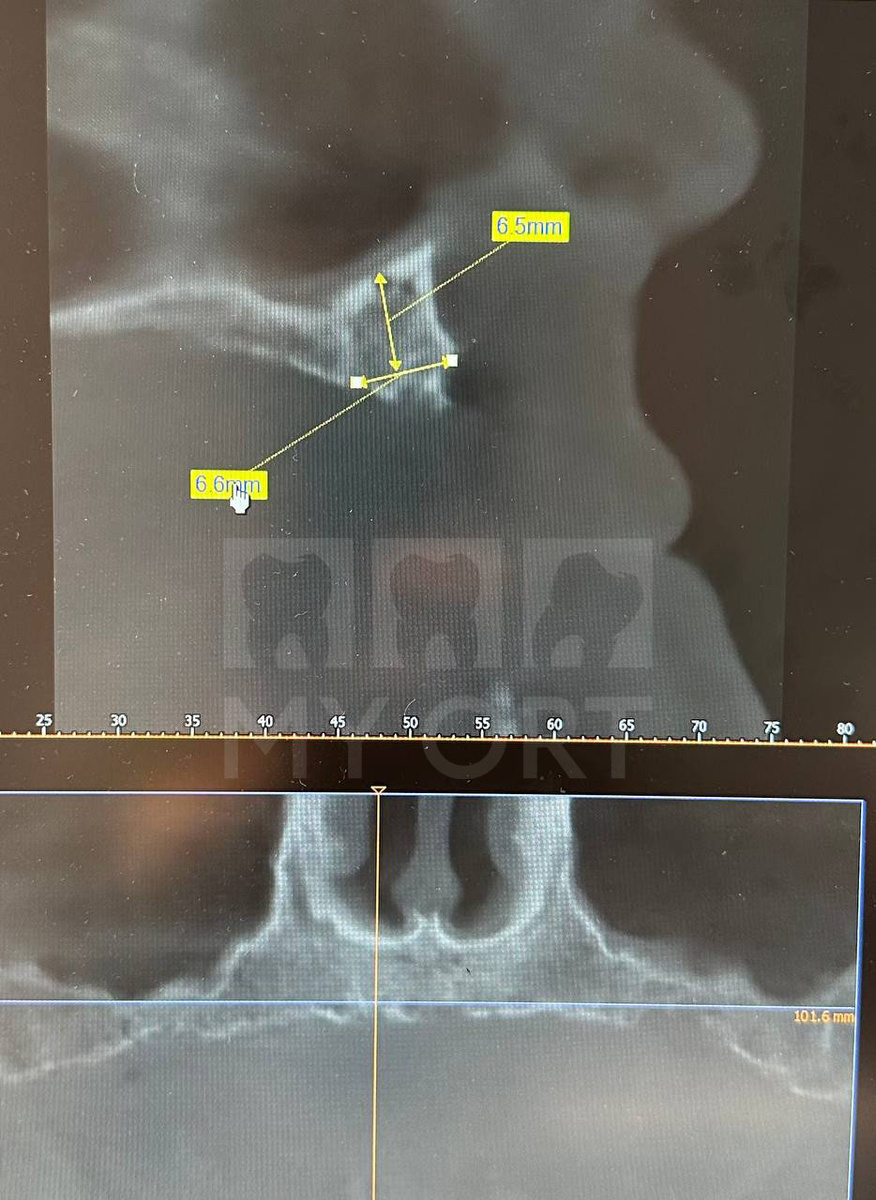

Пациентке была проведена комплексная диагностика: клинический осмотр и анализ особенностей улыбки, оценка прикуса, объёма мягких и твёрдых тканей. Были сделаны КТ и 3D-снимок (КЛКТ) для определения анатомических ограничений. Взяты анализы крови.

Дефицит костной ткани в передних и боковых отделах верхней челюсти

При недостатке костной ткани в переднем отделе верхней челюсти невозможно установить имплантаты приемлемой длины. При назолифтинге приподнимается слизистая дна носовой полости, создается пространство для установки имплантатов, и их верхушки оказываются под слизистой «в носу». Это обеспечило надёжную фиксацию имплантатов в плотной кости дна носовой полости, позволило увеличить их длину, добиться высокой первичной стабильности и создать условия для немедленной нагрузки и долгосрочной службы конструкции.

Установка имплантатов. Снимок (КТ)